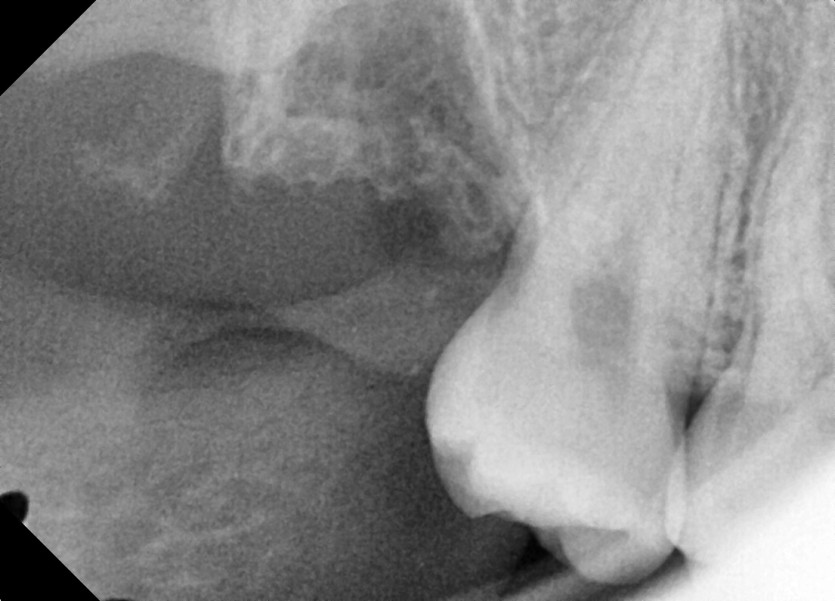

#18,28,38,48 사랑니 발치

구강 외과 전문의가 당일 발치했습니다.